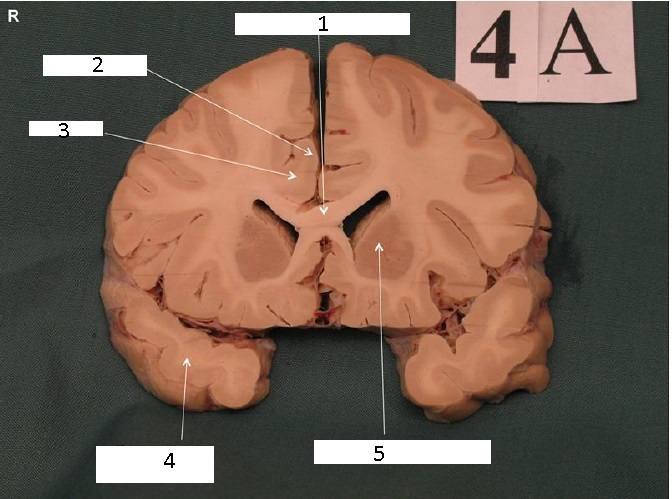

Identify 1

Body of Corpus Callosum

Identify 2

Head of Caudate Nucleus

Identify 3

Anterior Limb of the Internal Capsule

Identify 4

Putamen

Identify 5

Claustrum

Identify 6

Insula

Identify 7

Nucleus Accumbens

Identify 8

External Capsule

the lateral portion of the ‘A’ formed by the external and internal capsule

Identify 9

Cingulum

Identify 10

Cingulate Gyrus